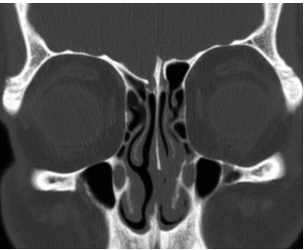

해 설 양측 전두개저 높이가 다른 경우로 우측 수술 시 좌측보다 전두개저 높이가 낮아 두개저 손상이 발생할 가능성이 있다.